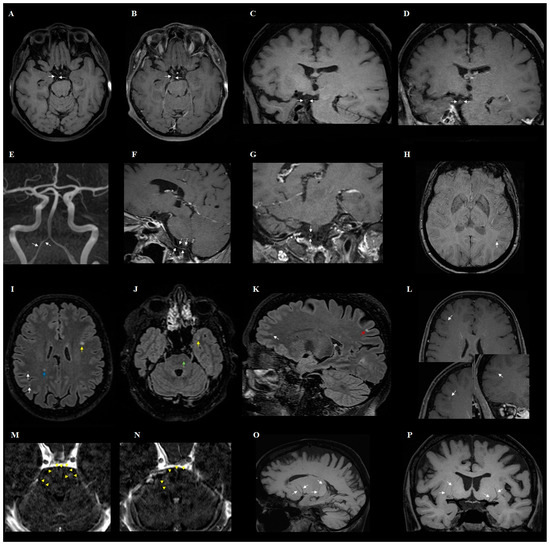

- The changes observed in post-COVID-19 patients were: hyperintense foci (in the white matter of the brain hemispheres, in the lower parts of the temporal lobes, and in the structures of the posterior cranial fossa), presence of engorgement of deep medullary veins or perivascular enhancement, presence of inflammatory (concentric) vessel thickening in VWI images, changes in hippocampus size according to the MTA scale, presence of cortical atrophy, and thickening of the mucous membrane of the paranasal sinuses.

- In addition to the characteristic changes in COVID-19, it was observed that the presence of atherosclerotic (eccentric) vessel thickening in VWI and the width of the third ventricle depend on the age of the patient.

| Presence of engorgement of deep medullary veins or perivascular enhancement (Figure 2) | 3 | 13% | ||

| Presence of inflammatory (concentric) vessel thickening in VWI images | 7 | 30% | ||

| Presence of atherosclerotic (eccentric) vessel thickening in VWI images | 11 | 48% | ||